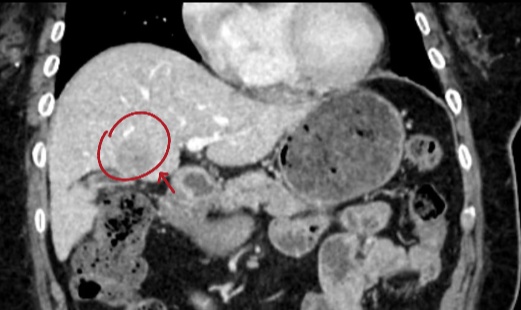

患者术前CT

利用术前CT,进行三维重建。